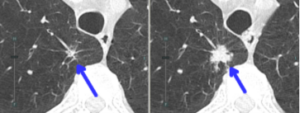

(CT画像 88歳 男性 喫煙歴なし)

X年 X年+11年

淡い影(すりガラス陰影)(緑の丸印の中の矢印部位)が見られます。11年間でその大きさが「増大」していることが分かります。

慎重に経過を観察し、このタイミングで手術を行いました。 その結果、病理診断は**「早期の肺がん(肺腺がん)」**でした。

(CT画像 78歳 男性 喫煙歴あり)

X年 X年+1年

白い塊(青の矢印部位)が1年の経過で急速に大きなっています。手術の結果は早期の肺がん(肺腺がん)でした。